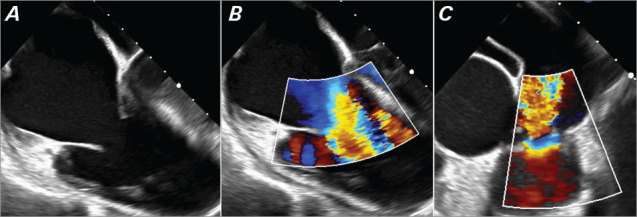

A 63-year-old man with a history of hypertension, prediabetes, and sleep apnea presented with pedal edema, weight loss, and flushing. Laboratory work revealed elevated B-type natriuretic peptide and normocytic anemia. Echocardiography showed right ventricular enlargement, severe tricuspid valve regurgitation, and thickened tricuspid valve leaflets, raising suspicion for carcinoid heart disease. Further testing confirmed a neuroendocrine tumor with liver metastasis. Despite somatostatin therapy, the patient's symptoms were refractory to diuretics. Surgical intervention with tricuspid and pulmonary valve replacement was undertaken. Postoperatively, the patient demonstrated substantial improvement in functional tolerance and quality of life. This case highlights the importance of surgical intervention in advanced carcinoid heart disease.